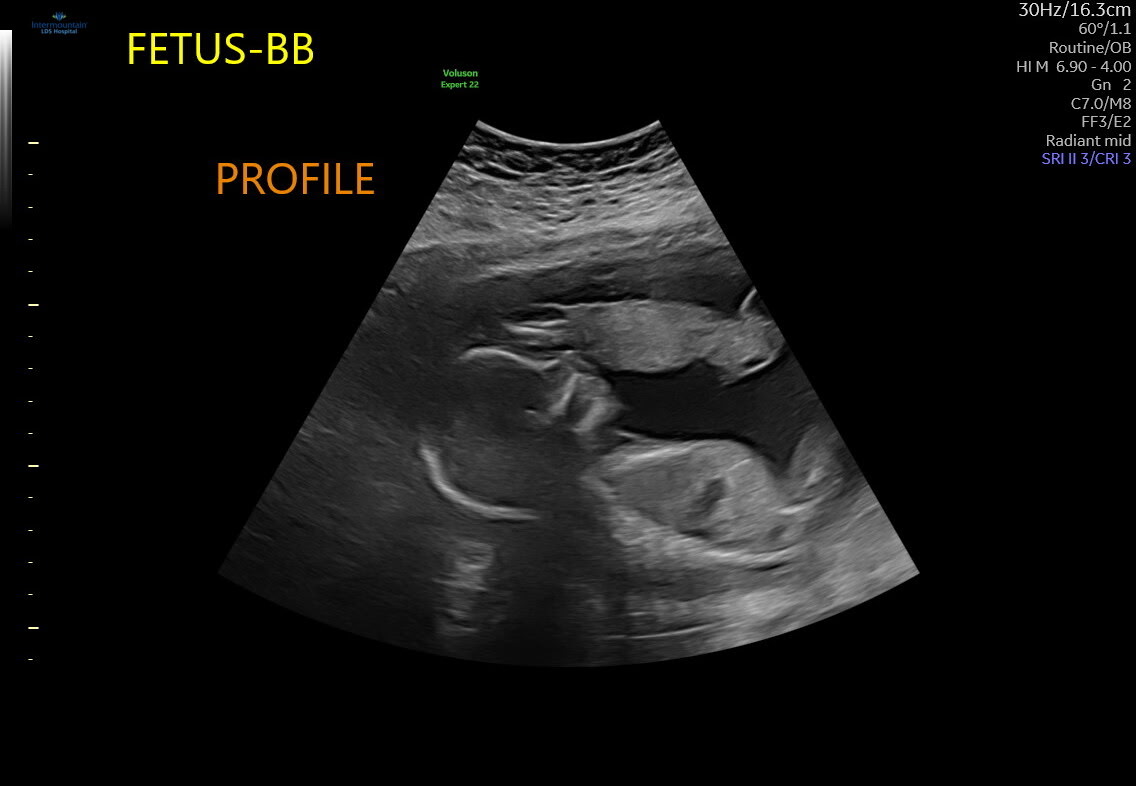

πΆπ Twin Baby Reveal ππΆ

Guess Baby B

Boy

Girl

π It's Twin Girls! π

πDue May 23, 2026π